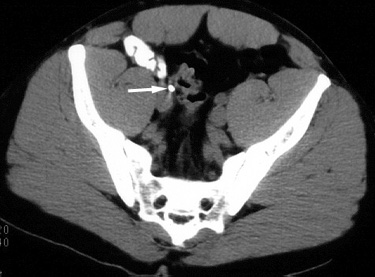

Figure 2. Contrast-enhanced CT image at the level of the midpelvis reveals a radioopaque calculus (arrow) in the right ureter. |

| The patient was given oral analgesic medications and discharged home from the emergency department. He spontaneously passed the calculus in his urine two days later and had relief of his symptoms. |